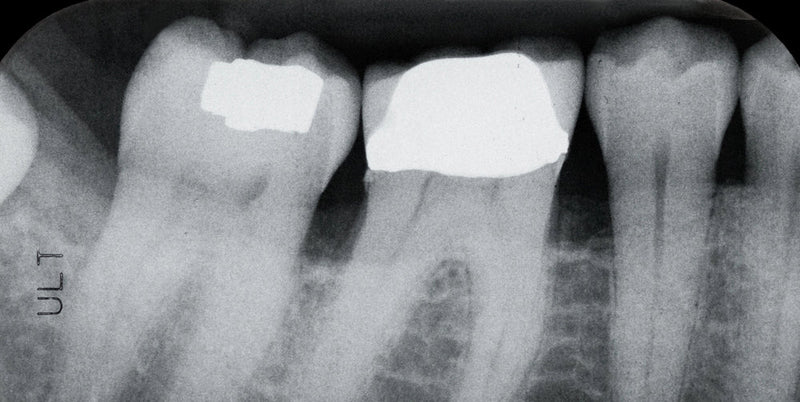

Today we're going to explore the world of cavities. Cavities, also known as dental caries, are areas of tooth decay that create holes in the teeth. They're often the result...